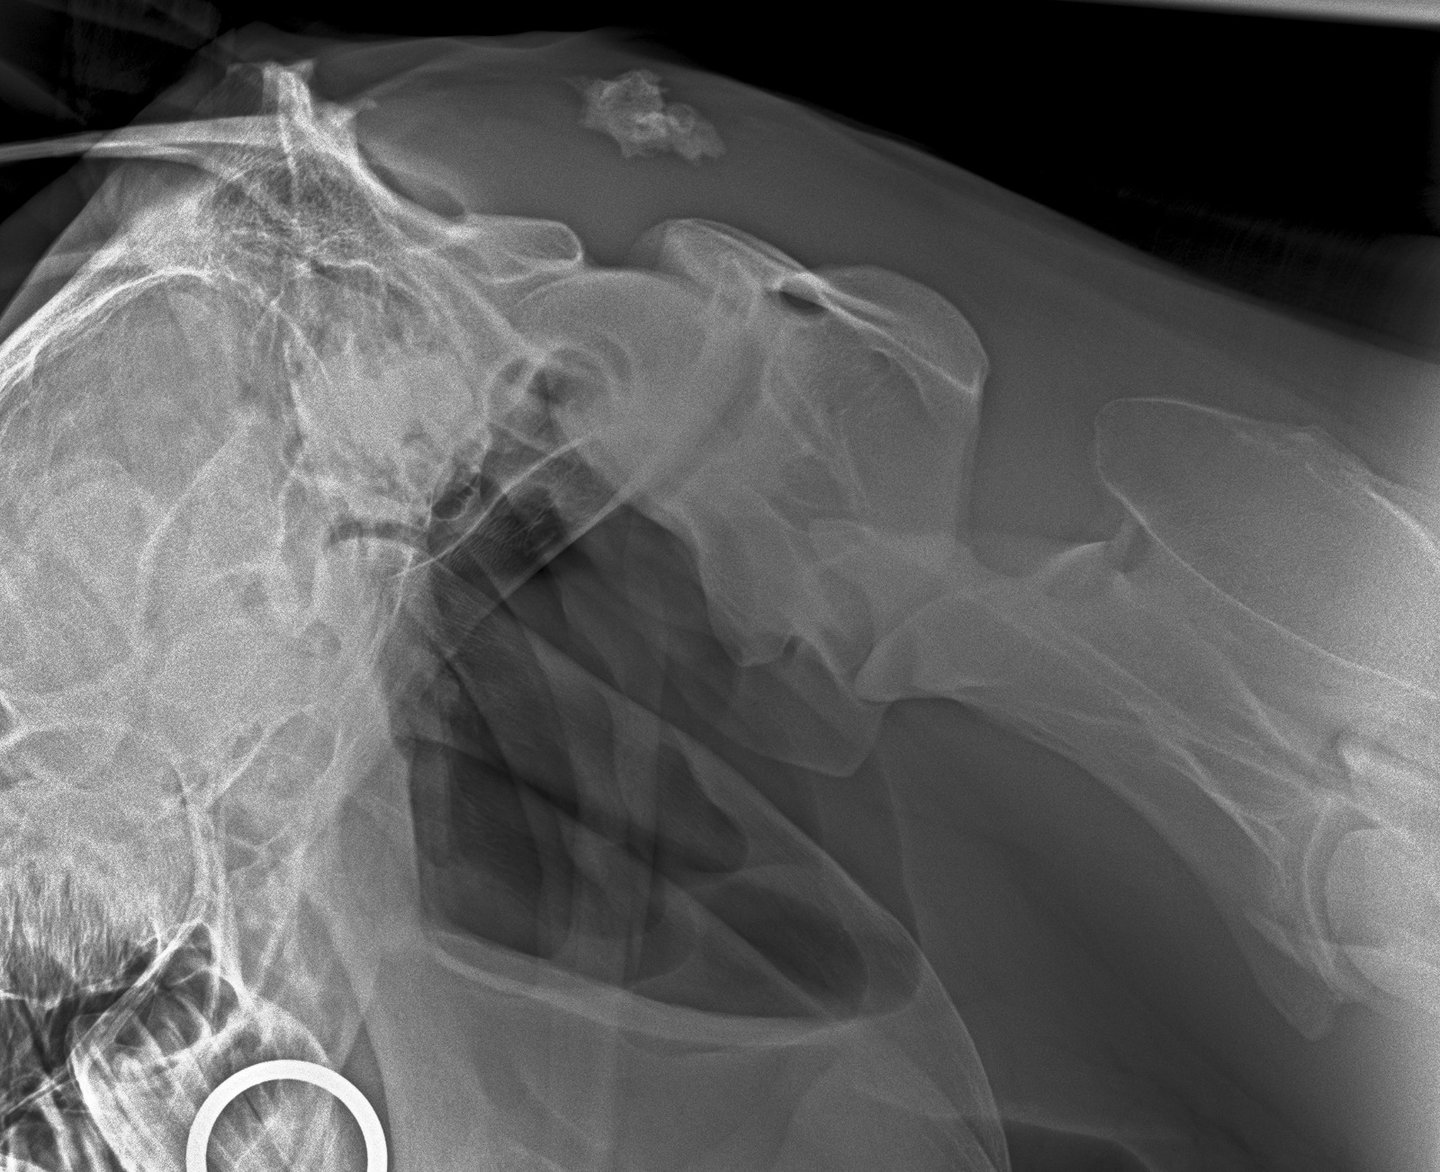

DIAGNOSTICO POR IMAGENES: ECOGRAFIA Y RADIOGRAFIA